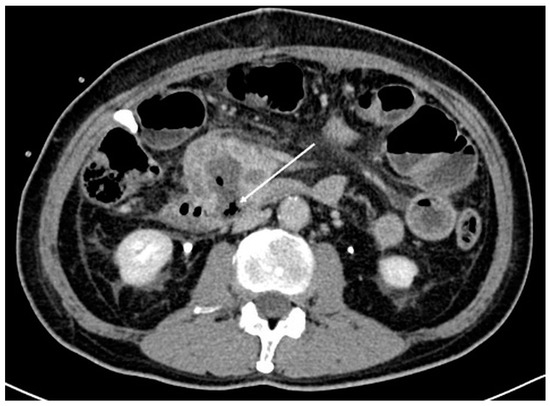

A 59-year-old man with an Eastern Cooperative Oncology Group (ECOG) performance status of 0 presented with LAPC of the uncinate process (biopsy proven pancreatic neuroendocrine carcinoma) with duodenal invasion (Figure 1A,B). The patient underwent a combination of chemotherapy and radiation therapy but was found to have stable disease.

Figure 1.

Axial (A) and coronal (B) computed tomography images of the patient demonstrating a heterogeneously enhancing pancreatic mass measuring approximately 6.3 × 4.4 cm. There is duodenal involvement by the pancreatic mass (arrows).